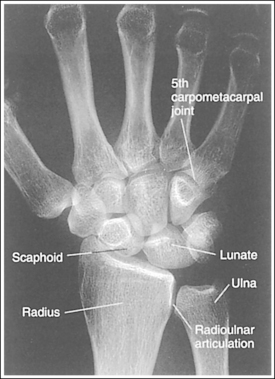

See Figure 4-29 and Box 4-11.

Contrast and density are adequate to demonstrate the scaphoid fat stripe.

• Significance of the scaphoid fat stripe. The scaphoid fat stripe is one of the soft tissue structures that should be visible on all PA wrist projections (Figure 4-30). It is convex and located just lateral to the scaphoid in an uninjured wrist. A change in the convexity of this stripe may indicate to the reviewer the presence of joint effusion or of a radial side fracture of the scaphoid, radial styloid process, or proximal first metacarpal.

The wrist is positioned in a PA projection. The radial and ulnar styloids are at the extreme lateral and medial edges, respectively, of each bone. The radioulnar articulation is open, and superimposition of the metacarpal bases is limited.

• Rotation of the wrist and forearm is controlled by the position of the hand, elbow, and humerus. A PA projection is accomplished by abducting the humerus until it is positioned parallel with the IR and the elbow is in a lateral projection. The hand is then pronated, placing the wrist in a PA projection (Figure 4-31).

The second through fifth CM joint spaces are open. The scaphoid is only slightly foreshortened, and the lunate is trapezoidal.

The long axes of the third metacarpal and the midforearm are aligned with the long axis of the collimated light field. The scaphoid and half of the lunate are positioned distal to the radius.

• If the long axes of the third metacarpal and the midforearm are aligned with the long axis of the collimated light field, the patient's wrist has been placed in a neutral position. If a neutral position is not maintained for a PA wrist projection, the shapes of the scaphoid and the position of the lunate are altered (Figure 4-33; see Images 36 and 37). Radial deviation of the wrist causes the distal scaphoid to shift anteriorly (toward the palmar surface) and to demonstrate increased foreshortening as it forms a signet ring configuration. The lunate will shift medially, toward the ulna. In ulnar deviation, the distal scaphoid tilts posteriorly and demonstrates decreased foreshortening, and the lunate shifts laterally, toward the radius. Radial and ulnar deviated PA wrist projections may be specifically requested to demonstrate wrist joint mobility.

Figure 4-33 PA wrist in radial deviation (left) and ulnar deviation (right). (From Martensen K II: Radiographic positioning and analysis of the wrist, In-Service Reviews in Radiologic Technology, 16[5], 1992.)

The carpal bones are at the center of the exposure field. The carpal bones, one fourth of the distal ulna and radius, and half of the proximal metacarpals are included within the collimated field.

• The wrist joint is located at a level just distal to the palpable ulnar styloid. To obtain an image of the carpal bones with the least amount of distortion, place a perpendicular central ray at this level and centered to the midwrist area. Open the longitudinal collimation to include half of the metacarpals. Transversely collimate to within 0.5 inch (1.25 cm) of the wrist skin line.